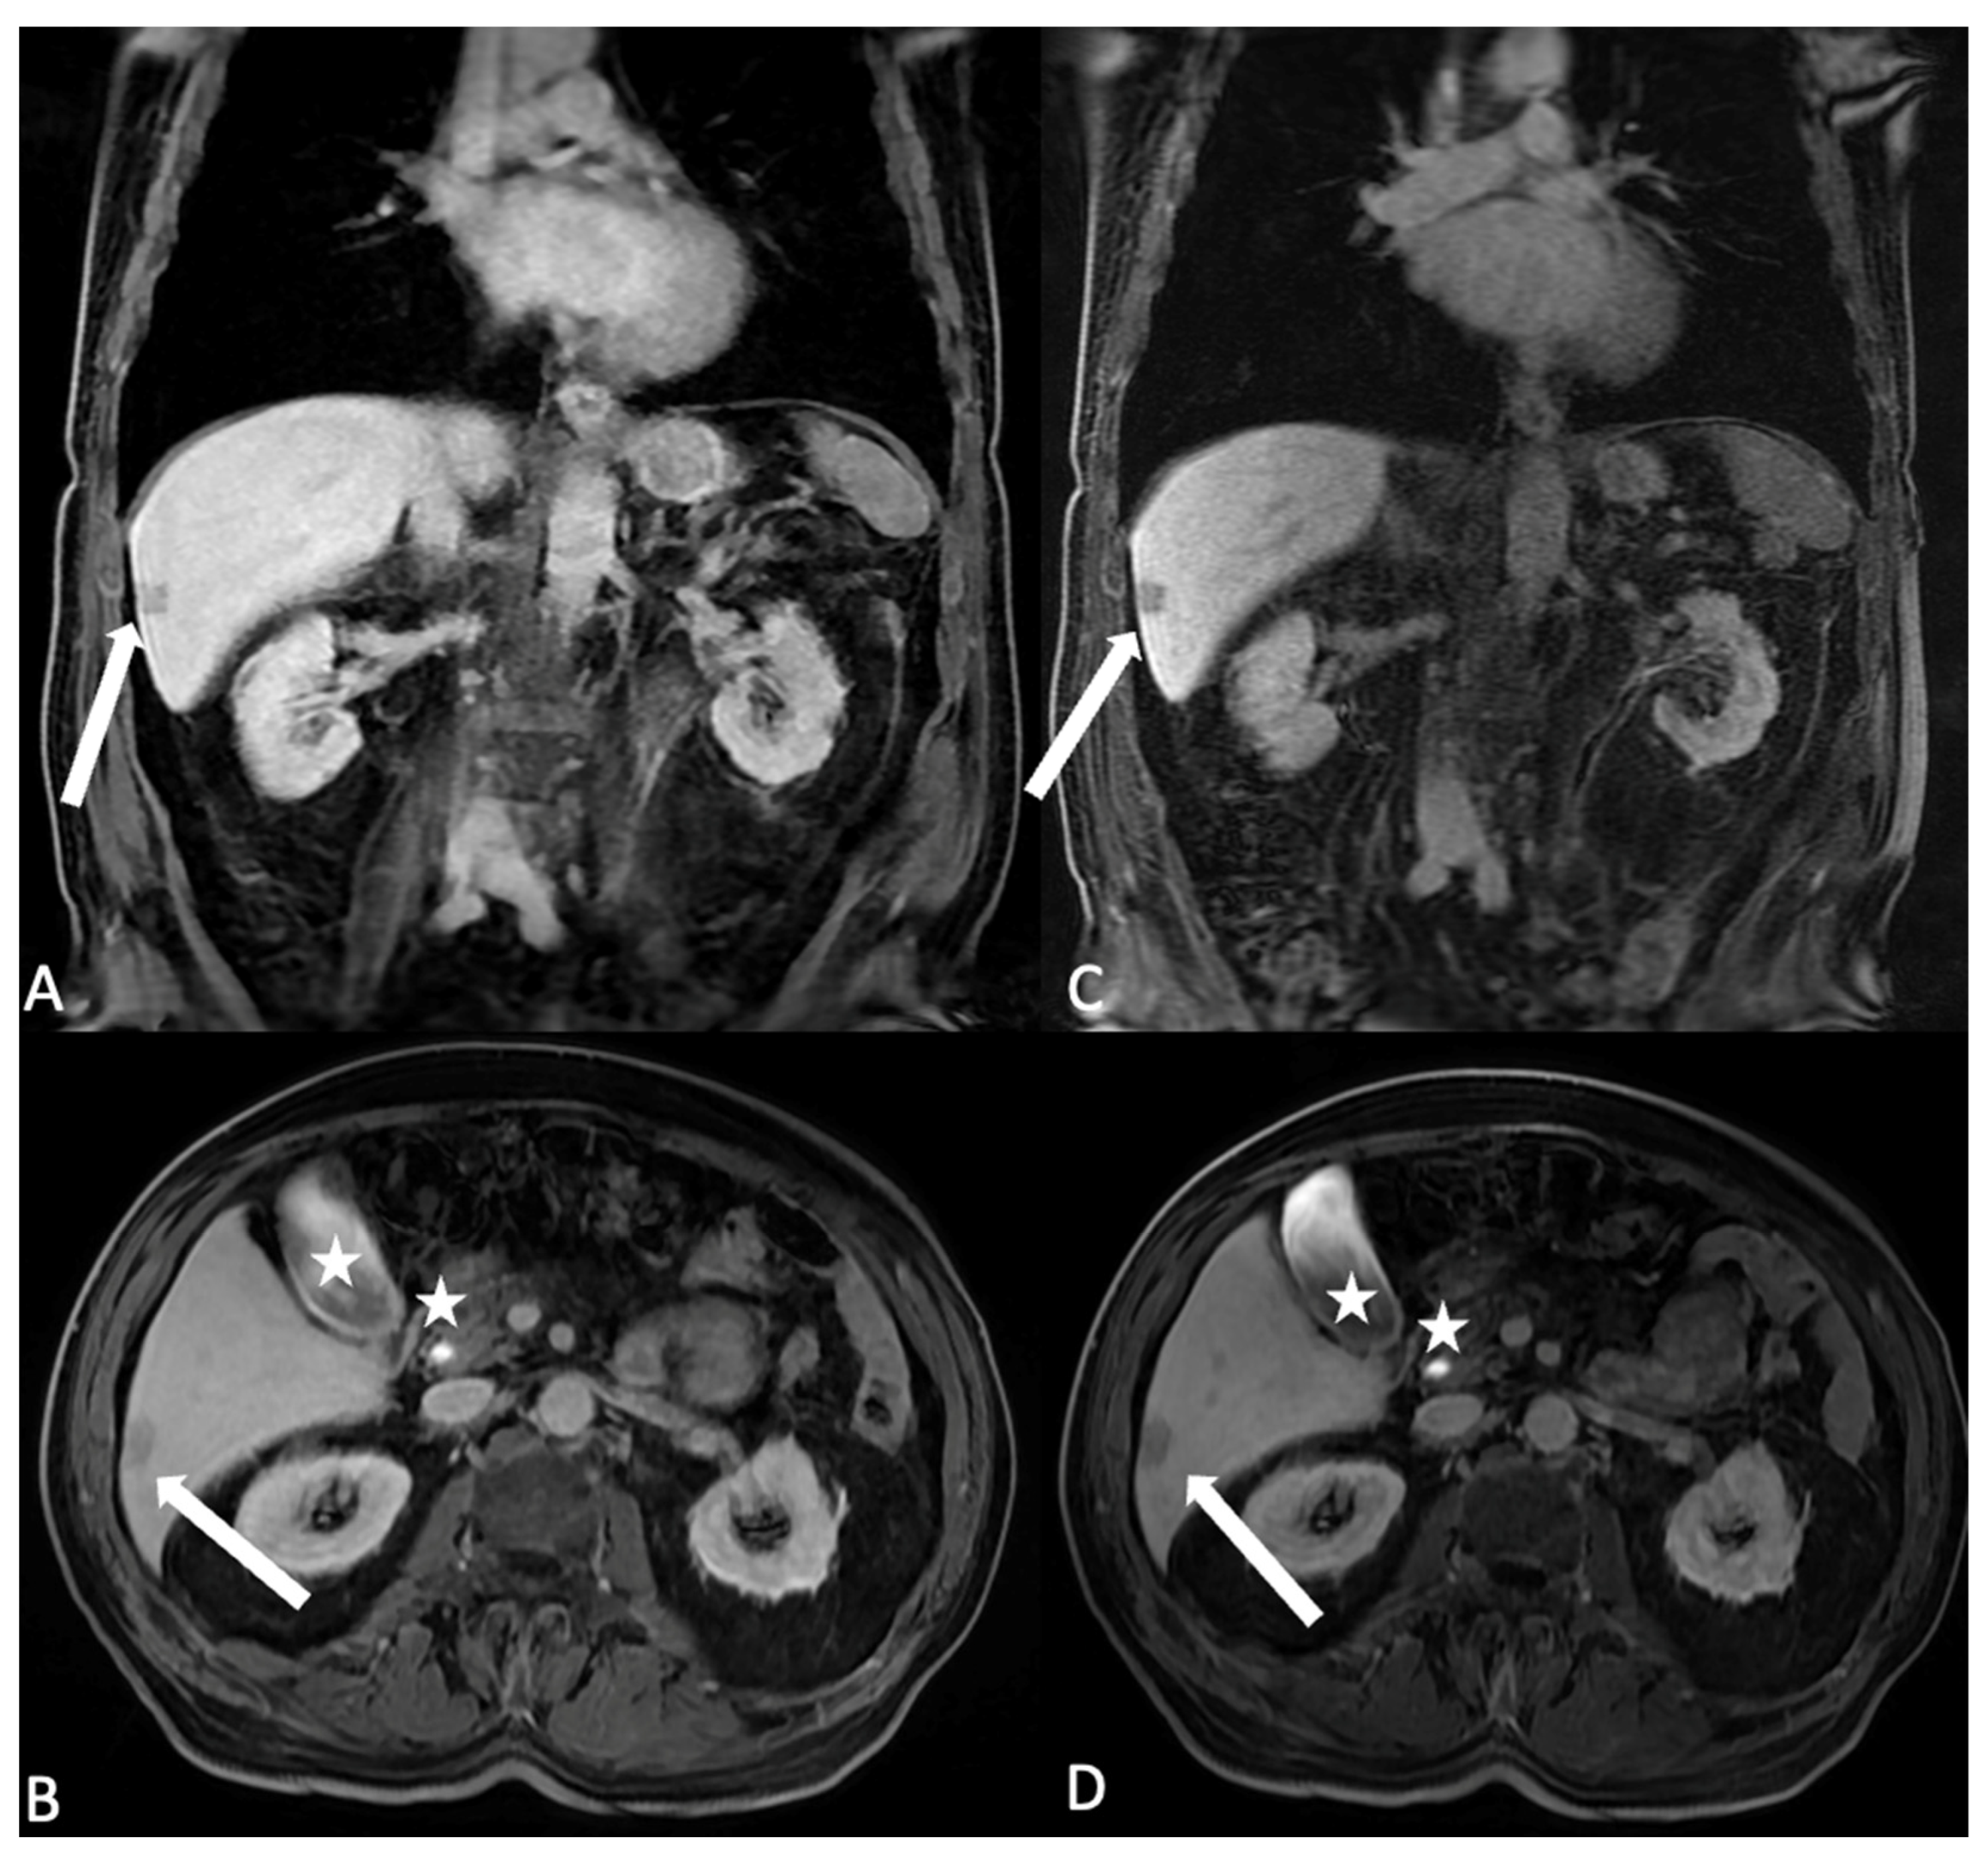

- Hepatocyte-specific contrast agents (HSCAs): Only two molecules are commercially available in this class (gadoxetate disodium and gadobenate dimeglumine); once intravenously injected, they undergo hepatocytes uptake. Their elimination is a combination of biliary and renal clearance (in particular, 50% of godoxetate disodium is excreted in the biliary system, thus with a shorter hepatocellular imaging window occurring approximately 20 min after injection and with a shorter total acquisition time compared to gadobenate dimeglumine of which just 5% is excreted in the biliary system). Due to their properties, HSCAs are mainly used for characterizing focal liver lesions, especially in chronic hepatopathies; off-label indications include bile duct imaging (both pre- or post-surgical or post-traumatic), gallbladder evaluation, and cystic duct obstructions [11,12,13].

- Seale, M.K.; Catalano, O.A.; Saini, S.; Hahn, P.F.; Sahani, D.V. Hepatobiliary-specific MR Contrast Agents: Role in Imaging the Liver and Biliary Tree. Radiographics 2009, 29, 1725–1748. [Google Scholar] [CrossRef] [PubMed]

- Di Serafino, M.; Iacobellis, F.; Ronza, R.; Martino, A.; Grimaldi, D.; Rinaldo, C.; Caruso, M.; Orabona, G.D.; Barbuto, L.; Verde, F.; et al. Hepatobiliary-specific magnetic resonance contrast agents: Role in biliary trauma. Gland Surg. 2023, 12, 1425–1433. [Google Scholar] [CrossRef] [PubMed]